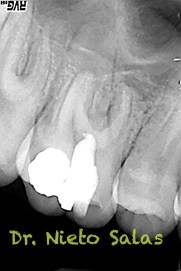

Sabemos que unas de las piezas que más fracasan, son estas piezas, pues, sin la ayuda de magnificación, es muy probable que dejemos alguna zona del sistema sin limpiar y mucho menos, obturarla.